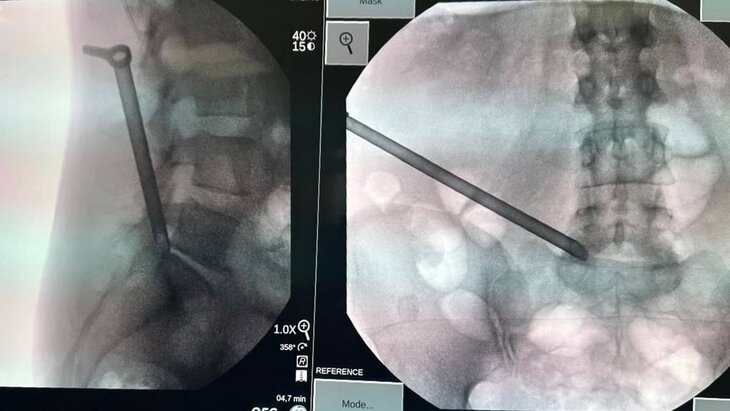

Фото: департамент здравоохранения Москвы

Нейрохирурги провели пациентке малоинвазивную операцию с использованием эндоскопической техники, позволившей успешно удалить воспаленные ткани без вреда для позвоночника и нервных структур. Продолжительность вмешательства составила 1 час 20 минут.